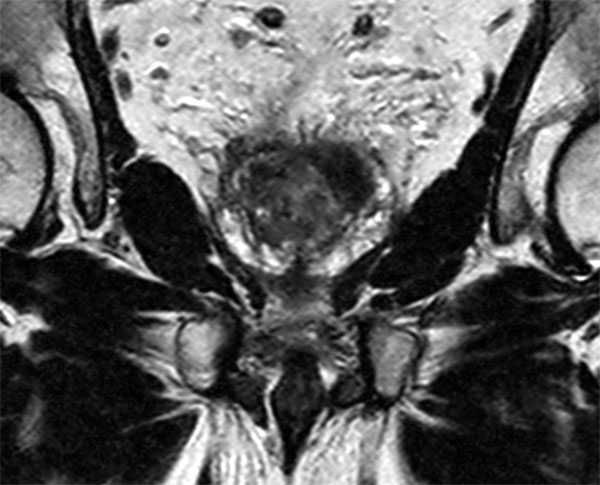

Coronal T2w TSE